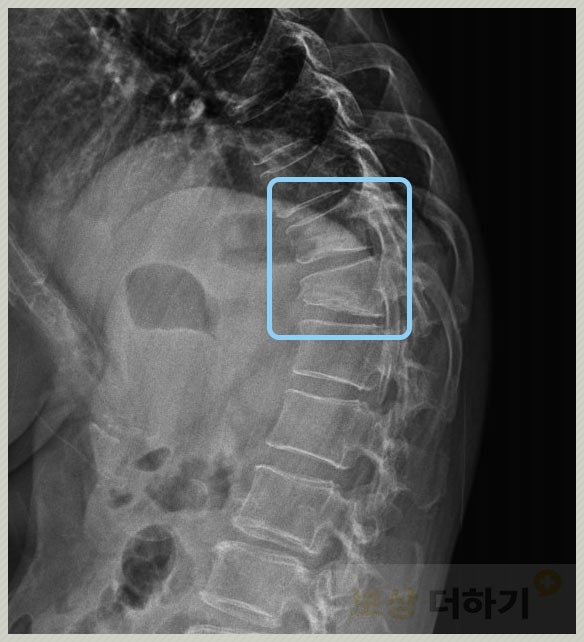

위 사진에서 골절이 된 척추체의 모양을 볼 수 있죠. 흉추 10번, 11번인데 손상이 안 된 다른 척추체와 비교하면 높이가 낮아진 게 육안으로 확인됩니다. 이렇게 한 번 낮아진 높이는 치료를 한다고 해도 온전히 돌아오지 않습니다. 즉 영구적으로 후유증이 남게 되며 이는 약관에서 후유장해로 인정하고 있어요. → 장애(후유장해) 보험금 청구 가능!